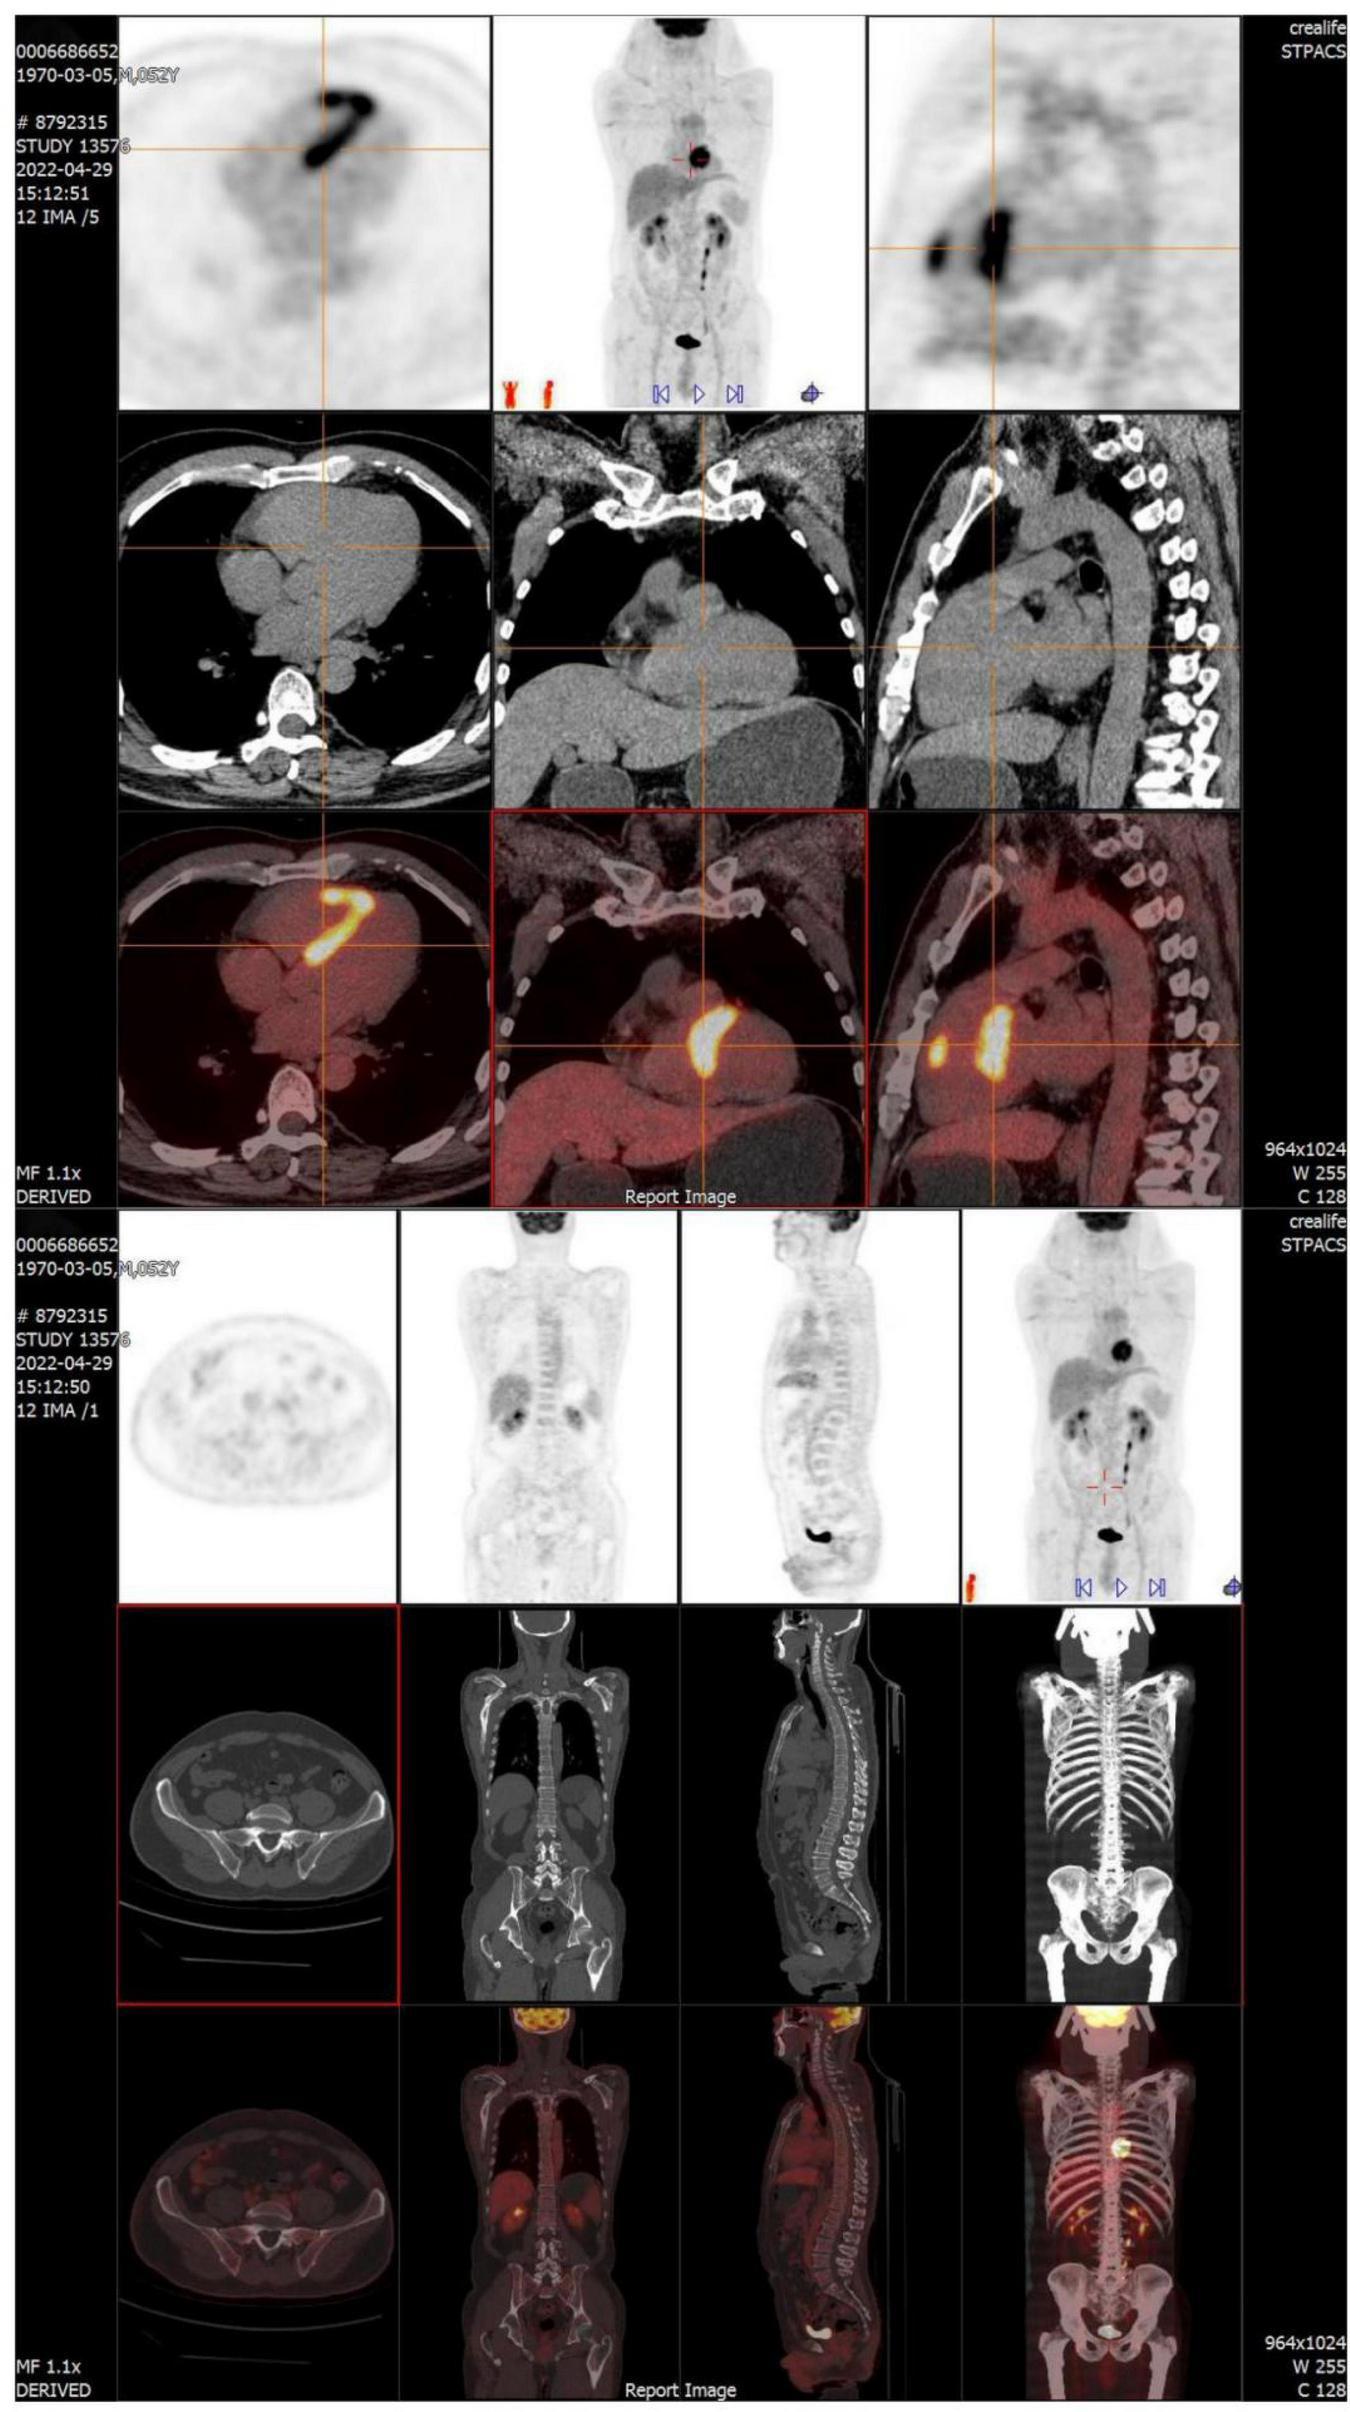

FIGURE 2

FDG-PET reveals intense multifocal cardiac uptake in the interventricular septum and right ventricle, and no abnormal lesions are found in other parts of the body. FDG-PET, Fluorine-18 fluorodeoxyglucose positron emission tomography.

Surgery and medication did not improve the patient’s symptoms within the following 7 months. In local hospital repeat CMR imaging showed that LGE was aggravated (Figure 1). Fluorine-18 fluorodeoxyglucose positron emission tomography (FDG-PET) demonstrated intense multifocal cardiac uptake in the interventricular septum and right ventricle without abnormal lesions in other parts of the body (Figure 2). Adenosine technetium-99m (99mTc)-sestamibi myocardial perfusion imaging showed that blood perfusion was decreased in the middle and basal segments of the ventricular septum. The doctor considered that arrhythmia might be caused by cardiac tumor, and suggested that the patient should undergo cardiac biopsy in our hospital.

During 2 months after discharge, the patient had no symptoms of palpitations. The 24-h Holter monitoring showed frequent premature ventricular contractions without further ventricular tachycardia. FDG-PET showed that the area of increased glucose metabolism in the original lesion was reduced, indicating the effectiveness of immunosuppressive therapy (Figure 5).

FDG-PET showed that the area of increased glucose metabolism in the original lesion was reduced, indicating the effectiveness of immunosuppressive therapy.